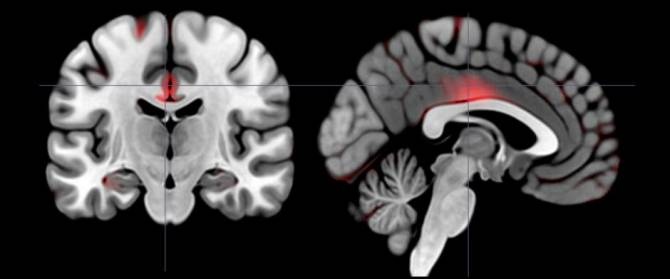

Mediante una técnica de morfometría, las investigadoras detectaron los volúmenes de materia gris en distintas regiones del cerebro. Las marcadas en rojo están asociadas con volúmenes más grandes en personas que exhiben el rasgo de personalidad de la extraversión movida por la ambición. (Imagen: Laboratorio de Tara White / Universidad Brown)

Pero además, entre las personas con niveles más altos de la extraversión alimentada por la ambición, hallaron varias otras regiones que tenían volúmenes de materia gris significativamente más grandes: el giro parahipocámpico (implicado en el aprendizaje y la memoria relativa a la recompensa), el giro precentral, el giro cingulado, y el caudado (involucrado en el control cognitivo del comportamiento y la iniciación, planificación y ejecución de acciones voluntarias hacia objetivos); y, entre los hombres en el estudio, el núcleo accumbens (involucrado en el procesamiento de las sensaciones de recompensa y de motivación, y que responde a estímulos como la comida sabrosa, el sexo y las drogas).

Así que, si bien ambos tipos de extravertidos tenían volúmenes más grandes de materia gris en una región cerebral clave, los movidos por la ambición también los tenían en varias áreas adicionales.